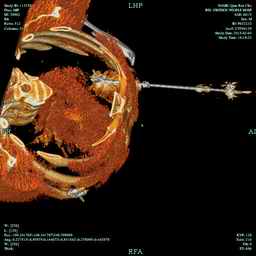

近日,我科成功为一晚期肺癌患者进行了射频消融术。家住鄞州区的钱大爷因反复咳嗽,痰中带血到我科就诊,当时CT提示钱大爷的左肺长了个3CM的肿块。收入院后,检查结果证实钱大爷得了晚期肺癌,且淋巴结已经转移。钱大爷以前一直喜欢抽烟,肺功能的情况也很差,如何给钱大爷制定诊治方案,是摆在医生面前的现实问题。俞万钧副院长针对患者多次组织科室讨论,制订了以射频消融为主联合化疗的诊治方案。整个手术只在胸前皮肤打了点麻药,手术过程中,钱大爷一直保持清醒,可以随时告诉医生术中的感觉。整个手术由俞万钧副院长现场全程指导,手术历时40分钟,对钱大爷的肺部肿瘤进行多点位叠加消融,术后钱大爷自诉除了除了一身热汗,无其他不适。

射频消融是近年盛行的原发和转移性肺癌有效治疗新技术。该方法疗效确切(有潜力达到类似外科切除效果)、创伤轻微、恢复快捷、生活质量高、可反复多次进行,具有极其光明的临床应用前景。肺癌射频消融是通过高热原理,使肿瘤组织发生凝固性坏死,从而彻底失去活性和转移潜能。目前肺癌射频消融所使用的电极针有多种类型,较常用者主要为“圣诞树样”或“伞状”电极,又以后者更符合肿瘤形态学特征、更为安全可控。(徐涛)